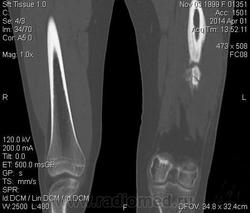

Молодая дама (14 лет) с переломом срдней трети диафиза левого бедра в анамнезе (декабрь 2012 г). Ломала ногу несколько раз в этом месте. Сейчас состояние после МОС. Как следует понимать изменения в кости, формируется ли ложный сустав?

Похоже ложный сустав сформировался. Но при нём обычно большие напластования костной мозоли, здесь их нет. В таких случаях смотрю при скопии подвижность.

Ох, не хочется думать о ложном суставе в 14 лет... По срокам под ложный сустав подходит, он характеризуется замыканием костномозгового канала с формированием подобий суставных поверхностей. У нее же есть хиленькая периостальная костная мозоль по задней поверхности бедра удерживающая отломки в правильном положении. Я склонна думать, что это скорее застарелый перелом (оно же замедленная консолидация). Здесь очень важно посмотреть предыдущие снимки (поиск рефрактуры, либо отсутствия полной консолидации).

Настоящего, родного ложного сустава пока нет, хотя костномозговой канал дистального отломка уже закрыт - образовалась склерозированная замыкательная пластина. Варусная деформация почти в 165 градусов... Я бы заключилась неполной консолидацией и варусной деформацией, прогностически формирование ложного сустава очень вероятно.